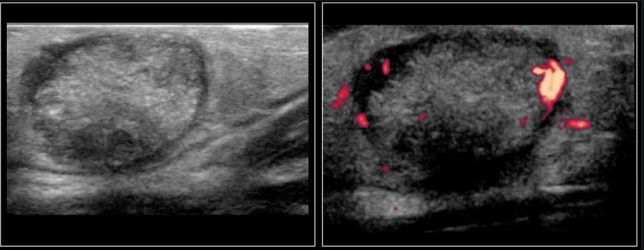

vascular paratesticular mass in a kiddo

think of?

Rhabdomyosarcoma

comes from epididymis or cord